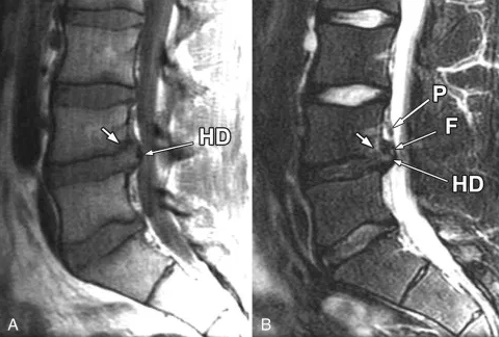

Hình ảnh MRI (cộng hưởng từ) của 1 trường hợp bị thoát vị đĩa đệm sau chấn thương.

HD: đĩa đệm bị thoát vị